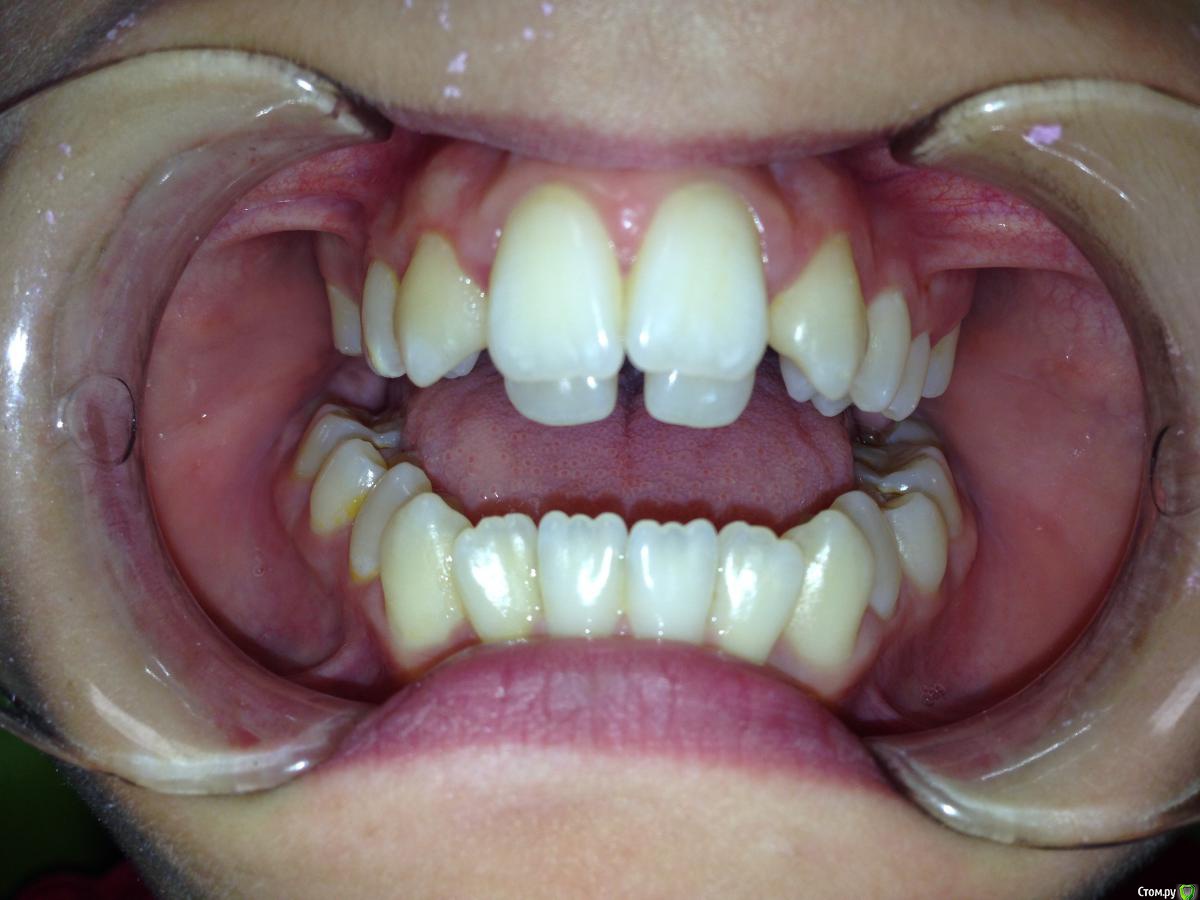

Алевтина Петровна Опубликовано 26 августа, 2015 Поделиться Опубликовано 26 августа, 2015 Всем добрый вечер. Я начинающий ортодонт. Надеюсь,что вы поможете с планом лечения. Пришел пациент. 13 лет. Ситуация по мне непростая, но очень интересная. Ссылка на комментарий

Алевтина Петровна Опубликовано 26 августа, 2015 Автор Поделиться Опубликовано 26 августа, 2015 Прикрепляю дополнительные фото, извините за качество. Это моя первая публикация, пытаюсь разобраться. Ссылка на комментарий